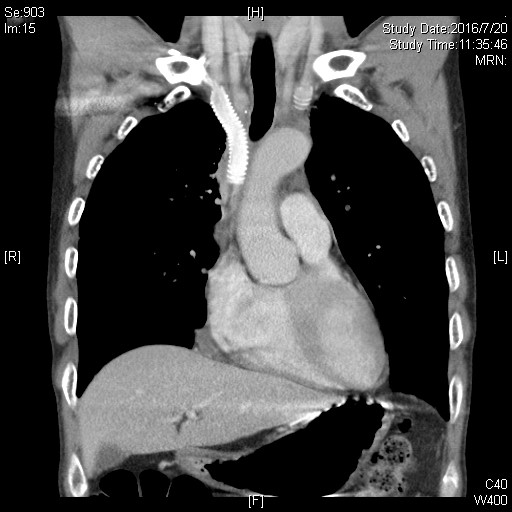

手术采用胸骨正中切口,进胸后细致分离肿瘤与胸骨间粘连,充分探查后可见肿瘤侵及左右无名静脉、上中段上腔静脉、双侧纵隔胸膜、双肺上叶前缘、右膈神经,同时与头臂动脉前缘及左膈神经关系密切。经过充分游离周围粘连、切除双肺受累部分、清扫上纵隔淋巴结、剥离左侧膈神经,切断约3cm受肿瘤侵犯的右侧膈神经。陈东红主任判断肿瘤具备切除条件,需进行上腔静脉重建。手术采用Gore-Tex带环人工血管行上腔静脉置换顺势吻合,以CV-6缝线连续缝合。先以人工血管建立左无名静脉-右心耳血管桥,完整切除肿瘤后搭右无名静脉-上腔静脉血管桥。检查吻合口无渗血,血管桥无扭转。而后由骨科潘勇卫主任进行了右膈神经的对端吻合。手术彻底肿瘤切除,人工血管充盈,心脏搏动有力。肺部切缘采取手工缝合,术后肺膨胀良好无漏气。切除肿瘤标本直径约10cm,手术时间约8小时。术后返回监护病房,3天内拔除所有引流管。

患者于术后8天顺利出院,手术3月后复查提示人工血管通常,患者无不适症状。透视证实膈神经功能恢复,两侧膈神经同步活动良好。